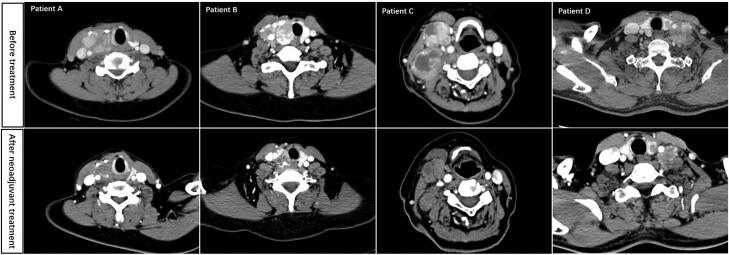

Effect and Safety of Apatinib as Neoadjuvant Therapy in Locally Advanced Differentiated Thyroid Cancer: A Phase 2 Trial.

This study was a multicenter, open-label, single-arm, phase II trial evaluating the efficacy and safety of apatinib as neoadjuvant therapy in patients with local advanced differentiated thyroid cancer (DTC).

Patients were treated with preoperative apatinib over a course of 2 to 4 cycles, culminating in surgical resection. The primary endpoints were objective response rate (ORR) and disease control rate (DCR); the secondary endpoints were the rate of R0 surgery, alterations in serum thyroglobulin levels, disease-free survival, and adverse events (AEs).

A total of 14 patients who met the inclusion criteria were administered neoadjuvant apatinib. Among these, 13 patients underwent surgical procedures following apatinib treatment and were enrolled in the ITT population. The ORR was 53.8% and the DCR was 100%. Of the patients, 84.6% received R0 surgery, while the remaining 15.4% underwent R1 resection. Predominant among the observed AEs were hypertension, hand-foot syndrome, hepatic dysfunction, proteinuria, and hypothyroidism, with no instances of grade 4 or 5 AEs reported. Subsequent to surgery, patients were followed up for a median period of 34 months, during which disease progression occurred in 5 individuals (35.7%), encompassing 3 cases of locoregional recurrences and 2 cases of distant metastases.

Apatinib may be an effective agent in the use of neoadjuvant therapy for locally advanced DTC. Patients may therefore benefit from surgical outcomes and their long-term prognosis.